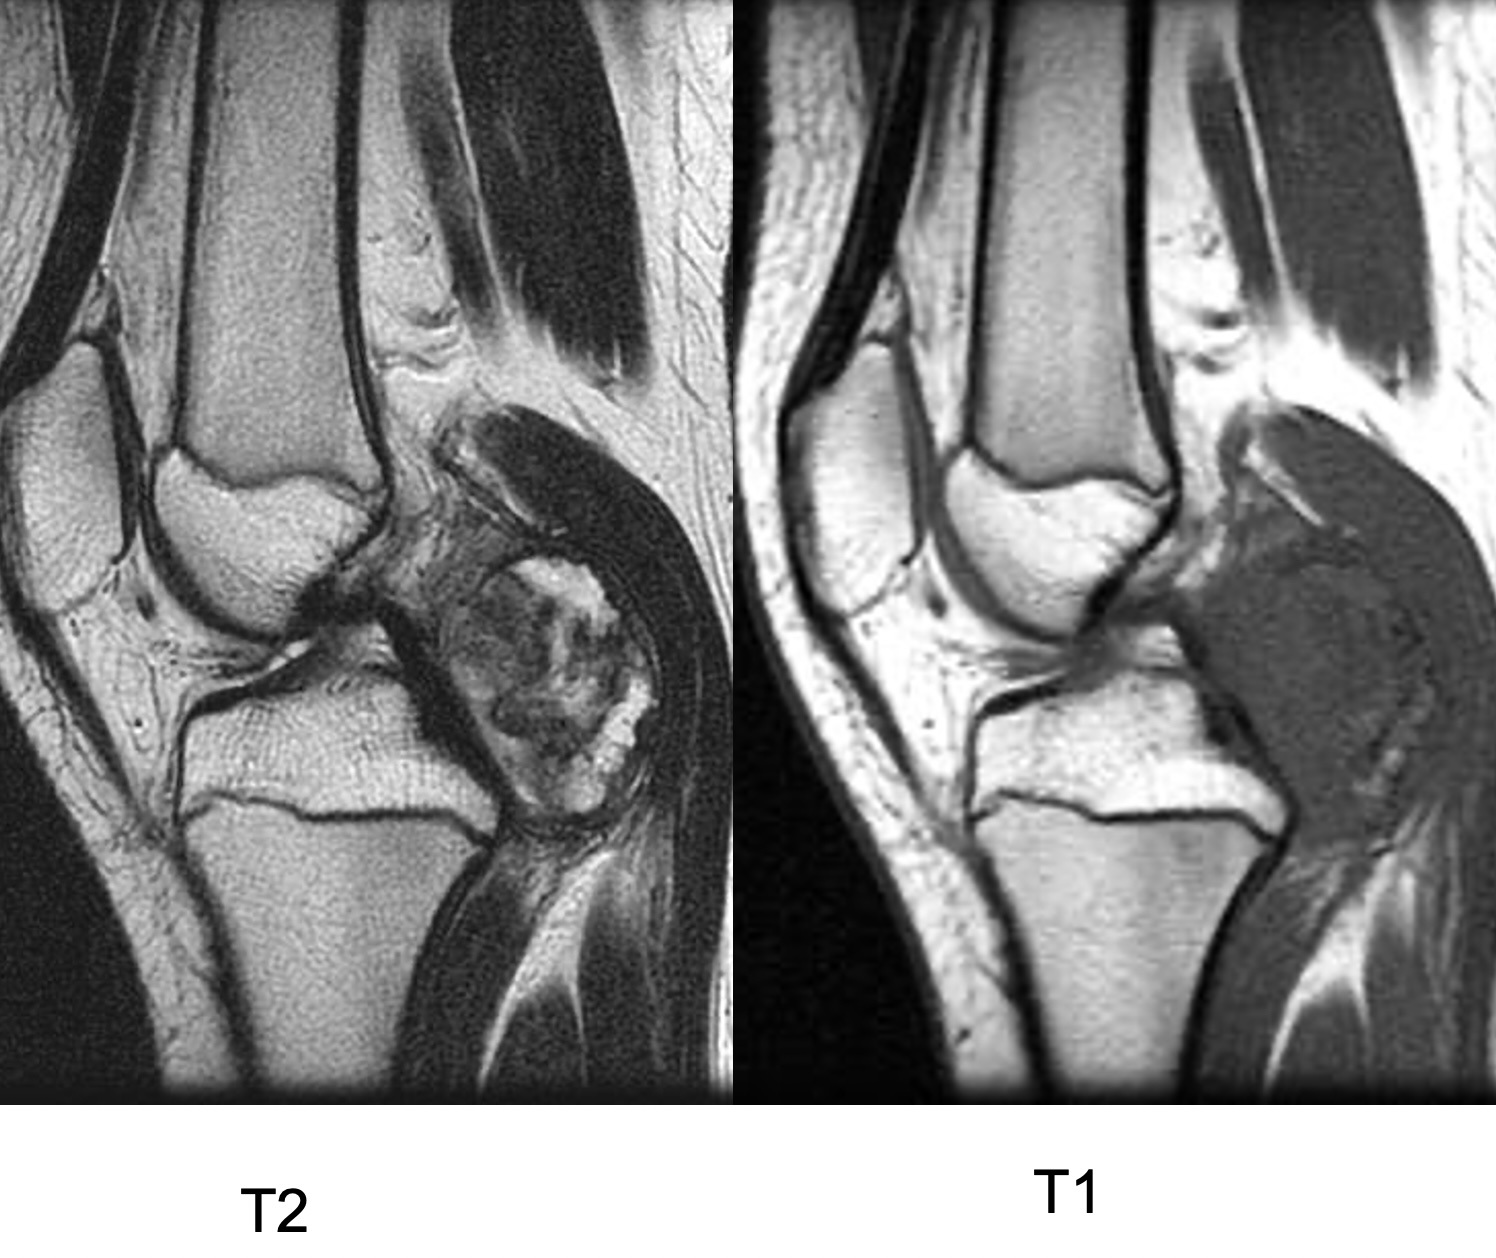

Figure 2 for case Synovial chondromatosis

Figure 2